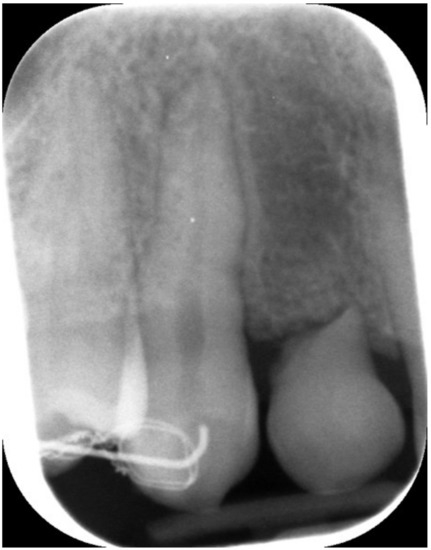

Figure 2.

Lateral preoperative view.

Figure 3.

Periapical X-ray showing deciduous canine.